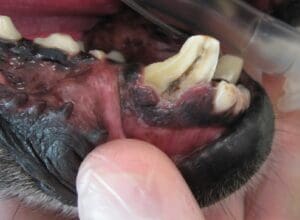

The large canine tooth is seen fractured here. The dark, central part is the pulp canal that is exposed.

The tooth is comprised of three main layers: the outer enamel, the middle dentin, and the inner pulp. The inner pulp canal contains living dental tissue made up of arteries, veins, lymphatics, connective tissues, and nerves. When the tooth is affected by fracture or pulpitis, it is the pulp that can be painful or become infected.